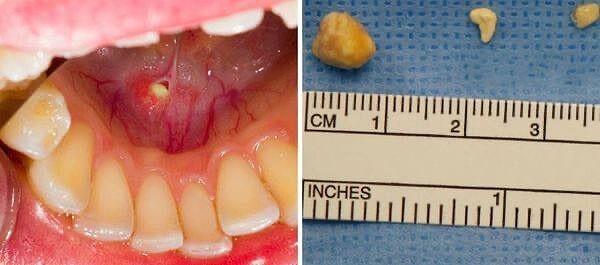

Камни в Челюсти! 😱😱😱😱😱

Это довольно редкая проблема, но периодически встречается. Образования представляют собой кальциевые отложения, образующиеся внутри протоков слюнных желез. Для непугливых: в единичных случаях приходится удалять всю слюнную железу. Но это крайне редко!   Своевременная медицина до сих пор не может дать 100% ответа на причины появления камней. Поэтому если чувствуйте изменения в полости рта – лучше сходить на консультацию к вашему стоматологу💙

Это довольно редкая проблема, но периодически встречается. Образования представляют собой кальциевые отложения, образующиеся внутри протоков слюнных желез.